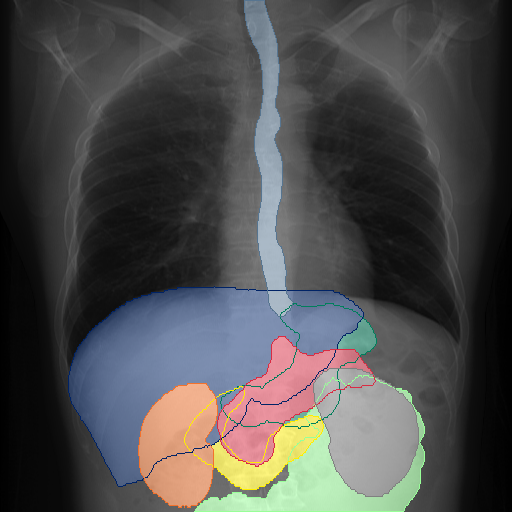

We show qualitative results for frontal projections in Fig. 2. We show a subset of classes belonging to the supercategories lungs, vascular systems, bones, and abdomen/digestive system. The predictions show minor deviations at the boundaries of the individual classes of the respiratory and vasculature system, while some inaccuracies become visible in the abdominal area. The qualitative results for the lateral projections are displayed in Fig. 2. Akin to the frontal view, the predictions show smoother borders but align with the ground truth. Apart from this, the segmentations provide matching insights on the thoracic anatomy with a slight deviation from the ground truth for both frontal and lateral views.

We display qualitative results in Fig. 3. The annotators tend to be content with most annotations. There are edits at the extensions of the esophagus, trachea, and aorta and corrections of the lower ribs. There is little consensus for classes in the abdominal area, such as the stomach, as seen on the right of Fig. 3 . In contrast, the annotators often align for bone classes.